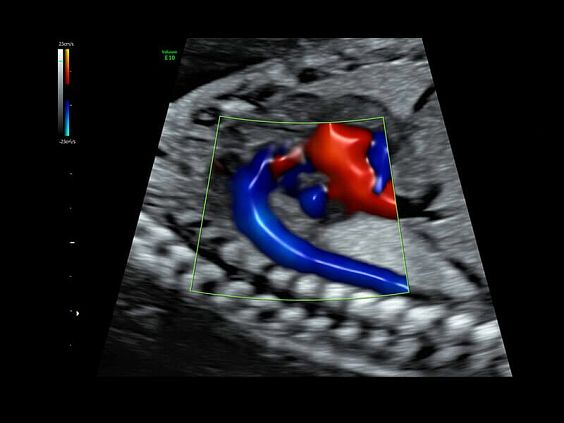

• HDlive Flow - перемещаемый источник света, совместимый с визуализацией кровотока в 3D

• HDlive Flow Silhouette - режим "Силуэт" с выделением границ полостей сердца и сосудов, совместимый с визуализацией кровотока

• Технология HDlive Flow — повышает реалистичность визуализации сосудистых структур, улучшая восприятие глубины (по сравнению с традиционным цветовым допплером и функцией HD-Flow).